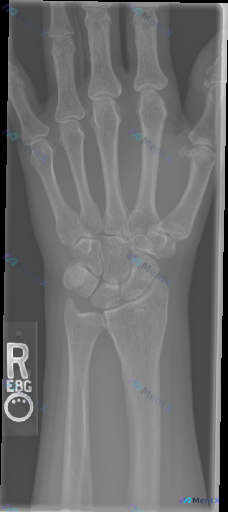

整理到一张右侧手腕X光正位片的影像资料,先把关键表现列出来,大家看看这种情况第一反应会往哪些方向考虑? 关键影像表现 1. 骨骼完整性: - 桡骨远端关节面可见横行透亮骨折线,累及关节面,骨皮质不连续,骨折端无明显移位; - 尺骨茎突可见撕脱性骨折征象,骨折块位置清晰; - 舟骨、月骨、三角骨等腕骨...

整理到一份右手及腕关节正位X光片的影像分析资料,分享给大家一起讨论。 影像观察到的关键信息: - 骨骼完整性:桡骨远端、腕骨序列、掌骨及指骨未见明确皮质断裂;但在尺骨茎突部位可见明显的皮质不连续,有一条透亮的骨折线,骨折块有轻微分离移位。 - 关节间隙与对合:桡腕关节、腕中关节及腕掌关节间隙清晰,腕...